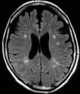

Chronic arteritis

Arteritis is the inflammation of the walls of arteries, usually as a result of infection or autoimmune response. Arteritis, a complex disorder, is still not entirely understood. [Source: Wikipedia ]